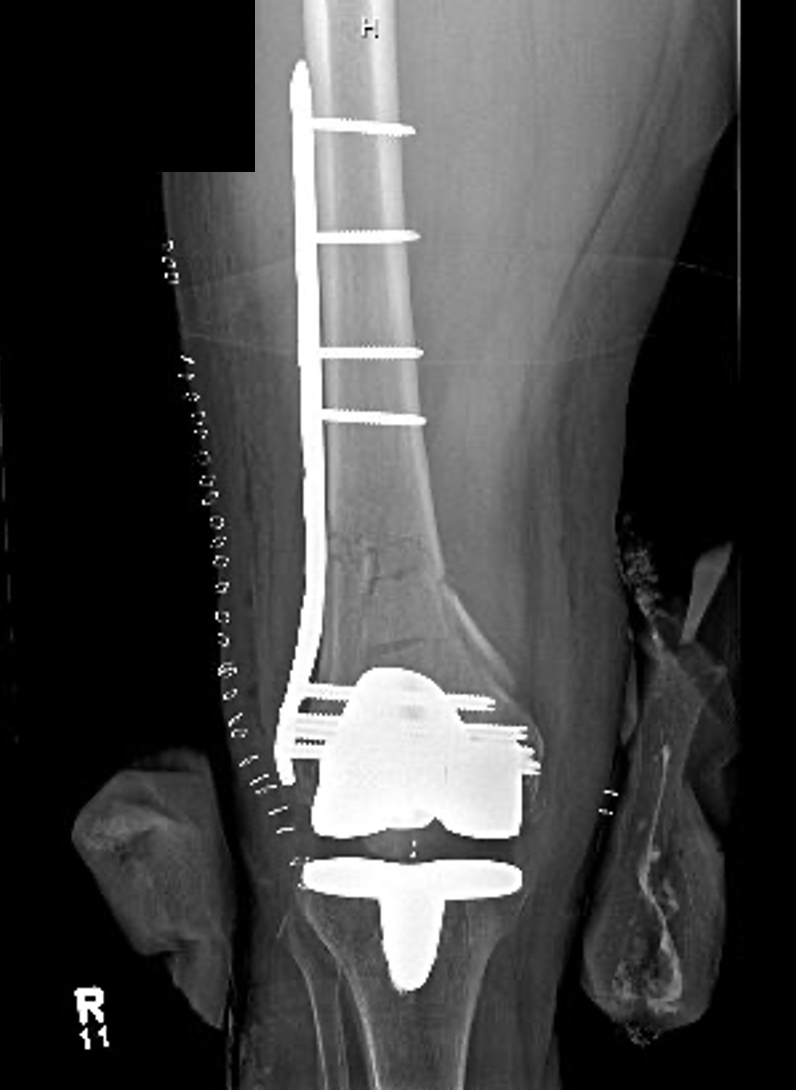

Prior to definitive fixation, 2/46 (4.3%) were treated in an external fixator, 40/46 (87%) in knee immobilizer and 3/46 (6.5%) in a splint and 1 in traction. On average, surgery was performed 2.09 days from injury (SD1.86, range 0-11days). Ninety-one percent (42/46) were approached through a lateral incision. The remainder had surgical stabilization through an anterior approach (9%). The majority of patients (42) were treated with a pre-contoured locking plate with the distal construct locked. The use of locking and non-locking screws varied. However, the majority of patients (36) were treated with all non-locking screws above the fracture or a hybrid construct of one or two locking screws above the fracture. Ten patients were treated with 3 or more locking screws above the fracture. In three patients, there were additional plates used for fracture stabilization (2 NWB, 1 EWB).

Radiographic union was determined by treating physician regarding presence of bridging callous. At week six 40/46 (87%) were deemed healed radiographically. There were two hardware failures (one at 6 weeks and one at 12 weeks), both in the NWB group. The remaining 4 fractures were all deemed healed at 12 weeks.

There were two hardware failures (one at 6 weeks and one at 12 weeks), both in the NWB group. Both patients had stainless steel plates. One of these patients did not desire additional surgery. This patient had 3 non-locking and one locking screw above the fracture. The other complication occurred in a patient treated with all locking screws above the fracture and underwent revision surgery.